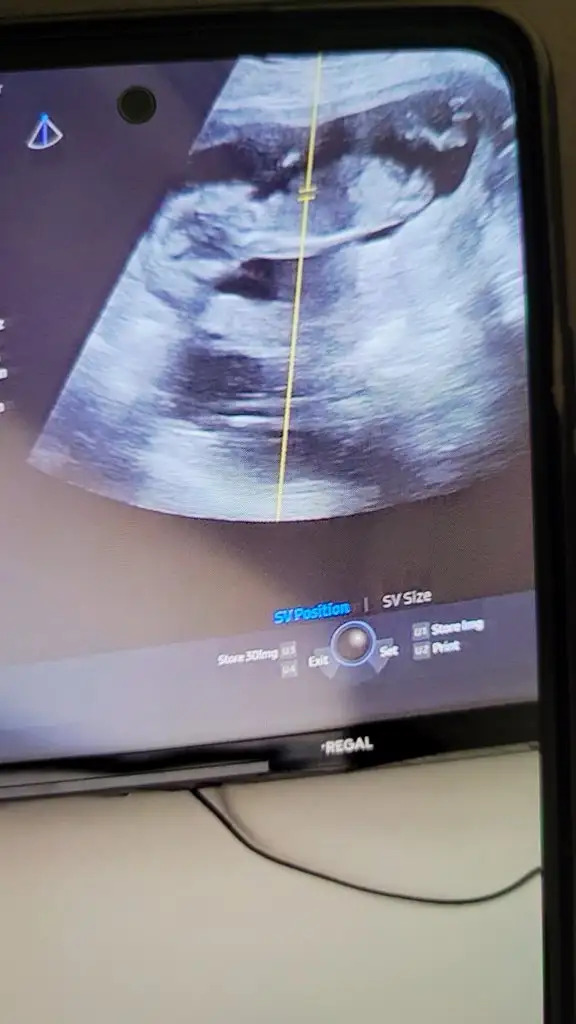

Kızlar banada tahminde bulunurmusunuz 12+5

Çok dikkatli şekilde baktım. Sivri çene için her ne kadar kız deseler de, nub hafiften yukarı bakıyor ve bu da erkek olduğunu gösteriyor. Sivri çene olup erkek olanını da görünce çeneye göre yorumlamak sanırım mantıklı gelmiyor bir yerden sonra, ama kız çıkarsa da nub belki pozisyonundan ötürü hafiften yukarı doğru bakıyormuş gibi çıkmış olabilir. Fakat ben yinede bebeğinizin erkek olduğunu düşünüyorum çünkü gerçekten de nub yukarı bakıyor.